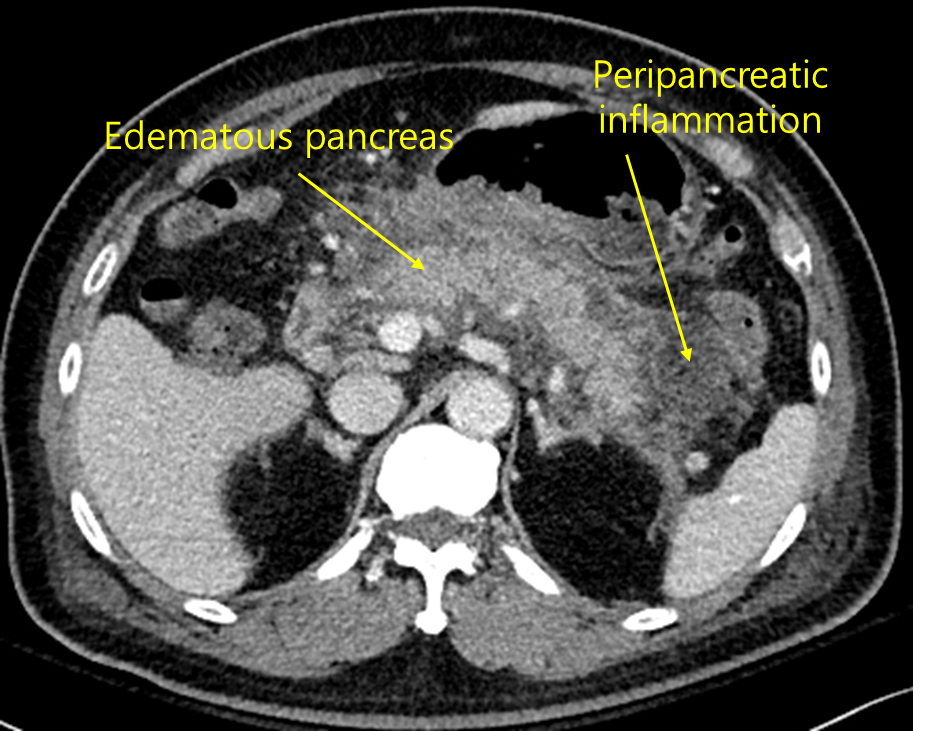

35세 여자가 하루 전부터 윗배가 아프다고 병원에 왔다. 일주일 전 술을 마신 다음 윗배가 자주 아프고 속이 쓰려서 위장약을 복용하였다고 한다. 혈압 100/65 mmHg, 맥박 110회/분, 호흡 20회/분, 체온 38.8℃이다. 장음이 감소되어 있고 복부전반에 미약한 압통과 반동압통이 있다. 혈액검사 결과는 다음과 같다. 복부 컴퓨터단층촬영 사진이다. 처치는?

백혈구 16,500/mm3, 혈색소 11.5 g/dL, 혈소판 130,000/mm3, 아스파르테이트아미노전달효소 42 U/L, 알라닌아미노전달효소 38 U/L, 아밀라제 3,500 U/L

Img | CT: 췌장 주위 fluid collection, 췌장의 불명확한 경계 |

임상양상과 amylase 상승, CT 소견으로 보아 급성 췌장염 의심 하, 금식 및 수액치료를 시행한다.

• CT상 실제로 pancreas 주위 fluid collection이 지저분하게 관찰되므로 급성 췌장염을 강력히 의심할 수 있다.

진단 | • US: 담석, 담관확장 확인 • CT: 췌장 실질의 edema, 췌장 근처 조직의 inflammation |